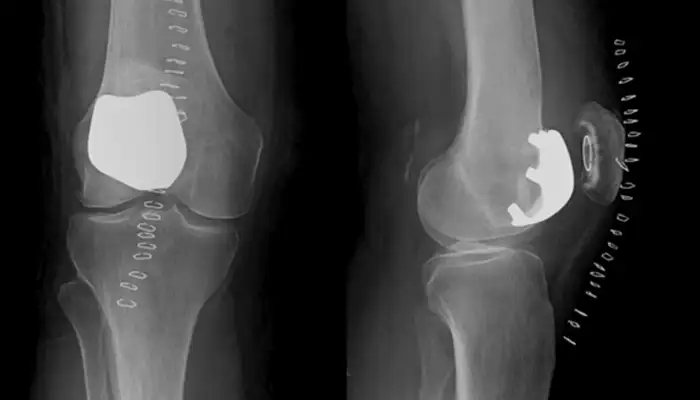

Osteotomia: Consiste en la realización de un corte controlado en la tibia o el fémur para corregir o cambiar el eje de carga y de esa manera, aliviar el dolor, función y los síntomas como consecuencia del desgaste en una parte de la articulación.

Se realiza en rodillas con una artrosis o desgaste de un compartimento y en gente joven y activa.